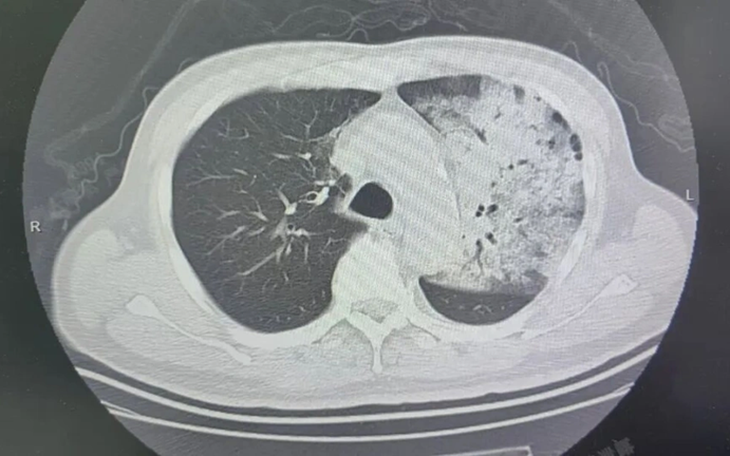

Sau khoảng một tuần điều trị tại bệnh viện địa phương, bệnh tình của ông đột ngột xấu đi. Bệnh nhân bắt đầu khó thở, rối loạn ý thức. Kết quả chụp CT cho thấy 2 phổi bị nhiễm trùng nặng, gần như “trắng xóa”. Dù đã được hỗ trợ thở máy nhưng tình trạng oxy máu vẫn không cải thiện.